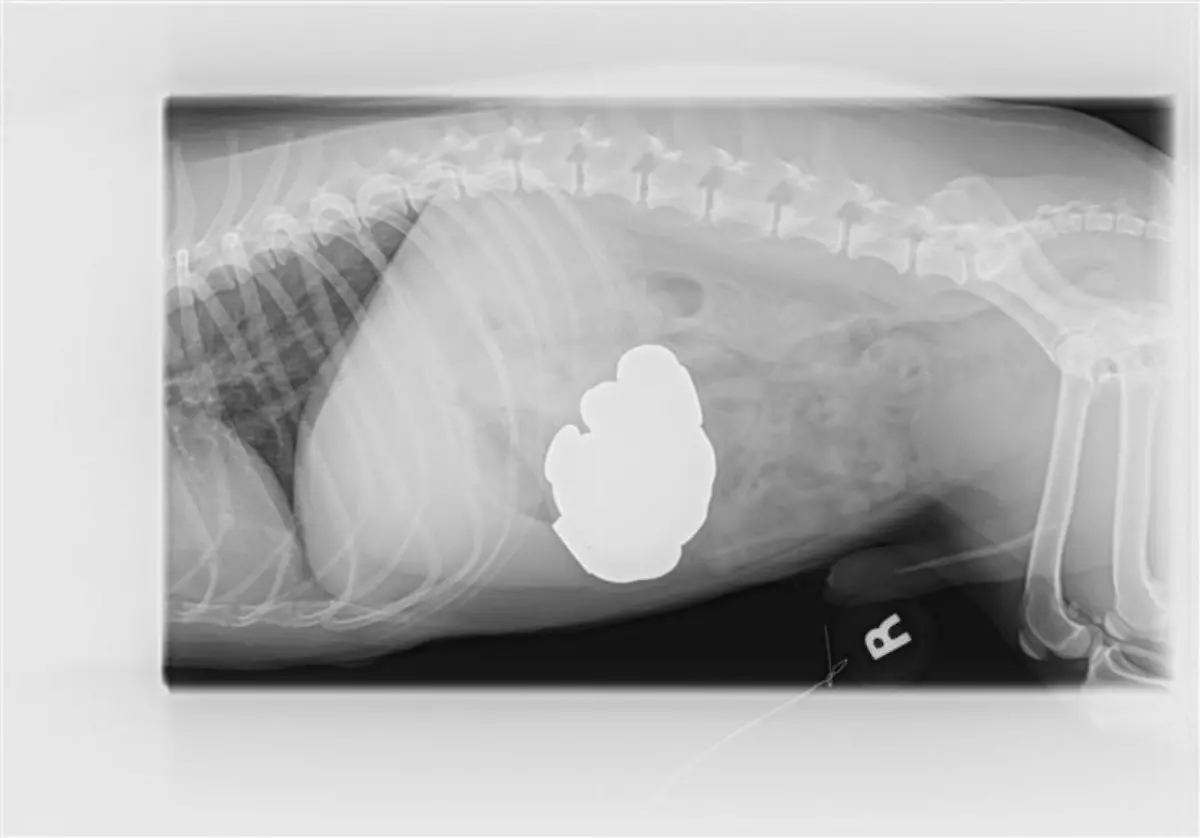

Socken, Kieselsteine, Außerirdische - Röntgenbilder von Mägen US-amerikanischer Haustiere zeigen die skurrilsten Gegenstände. Eine Zeitschrift zeichnet jedes Jahr die außergewöhnlichsten Aufnahmen aus.